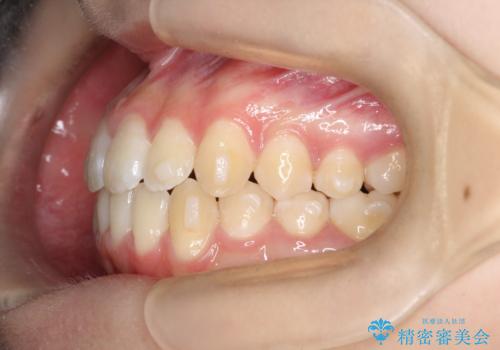

- 右上の小臼歯が大きくねじれており、噛み合わせや見た目に影響を与えている状態でした。診察の結果、インビザライン単独では十分な回転が得られにくいと判断。そのため、基本的な歯列の移動はインビザラインで行いながら、部分的にワイヤー矯正を併用するコンビネーション治療を計画しました。

まず、インビザラインで歯列全体を整えながら、スペースを確保しました。その後、部分ワイヤーを装着し、右上小臼歯の捻転を効率よく改善。ワイヤーの力を活用することで、より確実に歯の向きを整えることができました。治療後は、「しっかり噛めるようになり、見た目も自然になった」と患者様にもご満足いただきました。